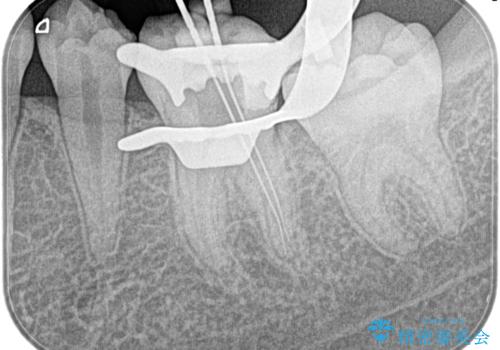

- 奥歯がズキズキ痛いことを主訴に来院されました。

検査の結果、診断を症候性不可逆性歯髄炎、症候性根尖性歯周炎とし抜髄を行っております。

根管充填はCWCT。

根管形成はマルテンサイト相を有するNi-TIロータリーファイル(NEX MS) 使用。